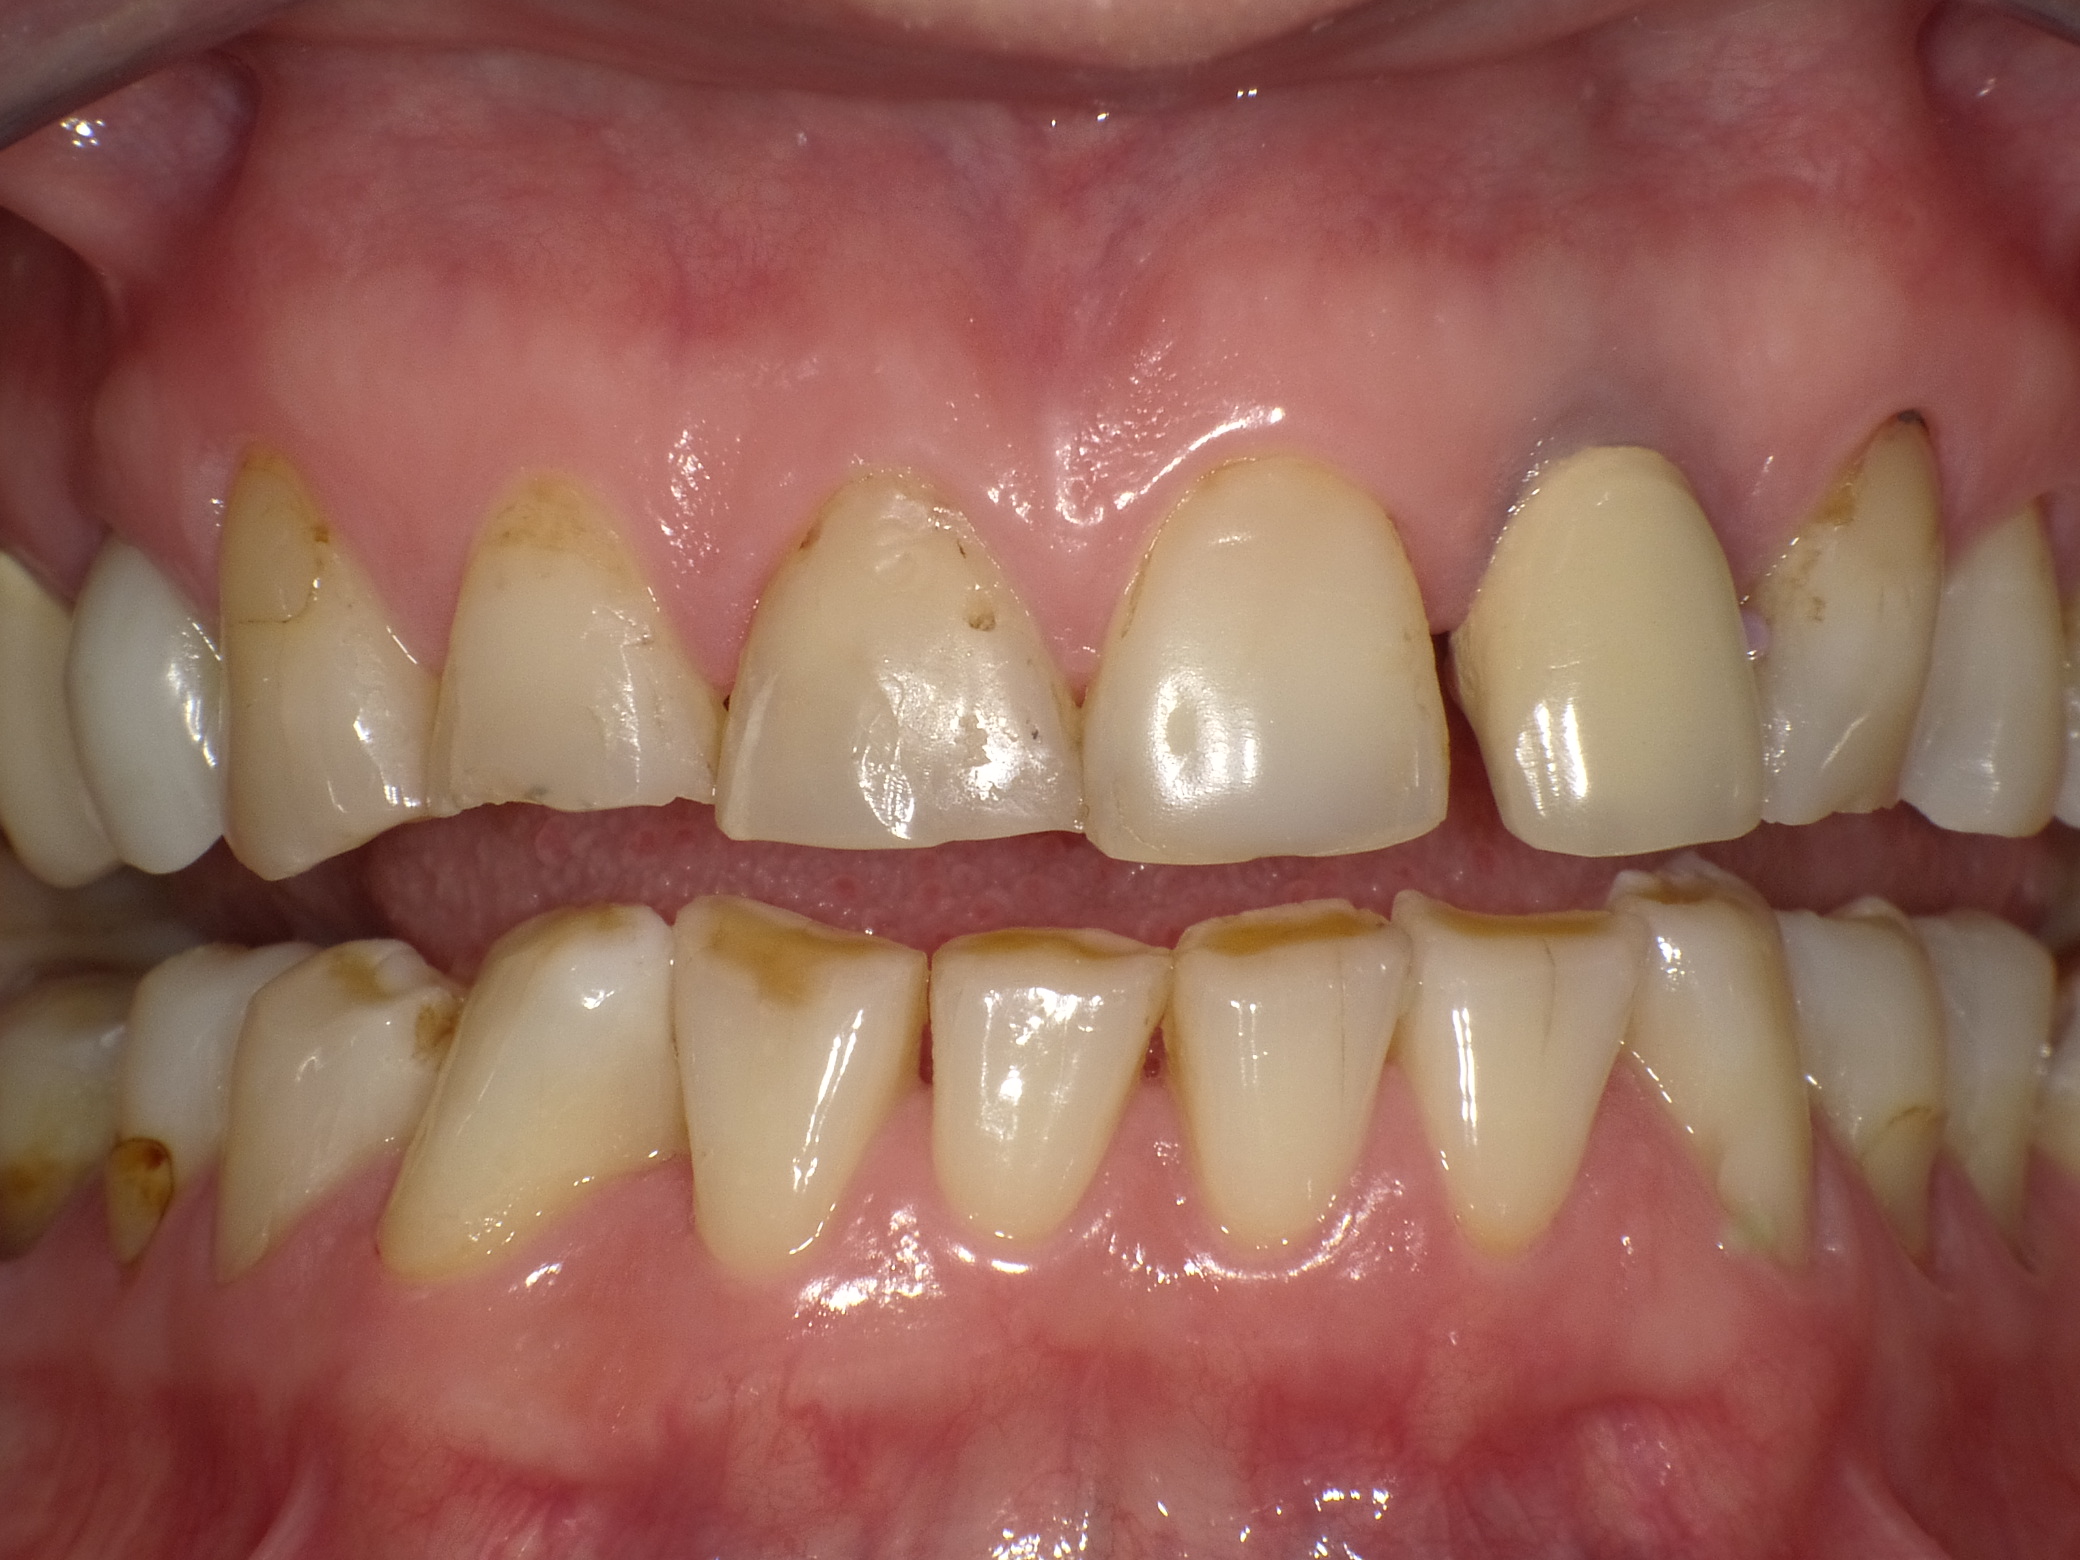

Unbefriedigende Ästhetik, vor allem aber Entzündungen im Knochen und eine massive Parodontitis mit bereits gelockerten Zähnen

Vorher: Unbefriedigende Ästhetik, vor allem aber Entzündungen im Knochen und eine massive Parodontitis mit bereits gelockerten Zähnen

Gesamtbehandlung in Sedierung: die Seitenzähne wurden durch Keramik-Implantate (Zahnentfernungen und Sofortimplantation) mit Knochenaufbau ersetzt; anschließend Gesamtüberkronung aus Vollkeramik mit Optimierung der Ästhetik

Nachher: Gesamtbehandlung in Sedierung: die Seitenzähne wurden durch Keramik-Implantate (Zahnentfernungen und Sofortimplantation) mit Knochenaufbau ersetzt; anschließend Gesamtüberkronung aus Vollkeramik mit Optimierung der Ästhetik